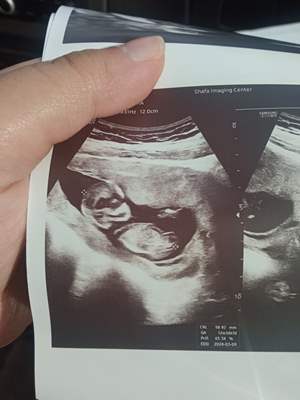

سلام همگی ، متخصصان تعین جنسیت از روی عکس سونو ان تی ، لطفا یک لحظه تشریف بیارید